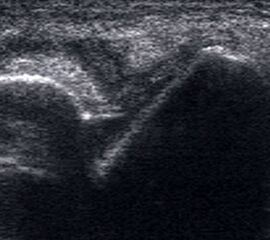

Mithilfe von Ultraschall (siehe auch „Sonographische Diagnostik an Sprunggelenk und Fuß“) lässt sich in der dynamischen Untersuchung eine Instabilität nachweisen 28. Ein Kalibersprung des Bandes sowie ein von Flüssigkeit umspülter Bandstumpf sind weitere sonographische Zeichen einer Bandruptur (Abb.3). Das Untersuchungsverfahren kann bei medialen Instabilitäten ebenso eingesetzt werden wie bei der lateralen Instabilität 29. Auch zum Ausschluss von Syndesmosenverletzungen hat die dynamische Ultraschalluntersuchung eine sehr hohe Sensitivität und Spezifität 30. Beurteilt wird in Höhe der Syndesmose die Translation der Fibula gegenüber der Tibia im Seitenvergleich.